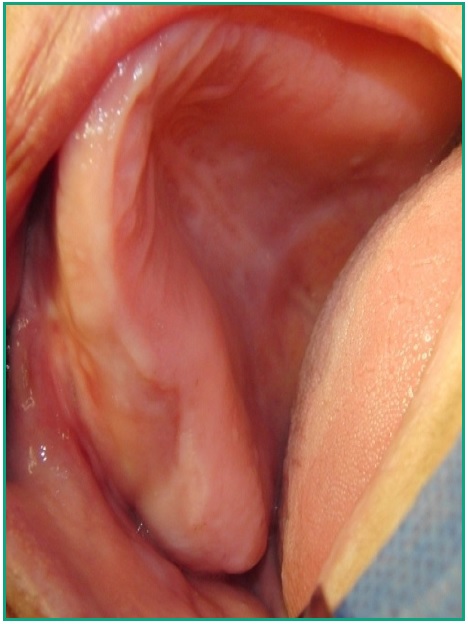

Caso clínico. Paciente de 68 años, sexo femenino que consulta en el Servicio de Urgencia de la Facultad de Odontología, Udelar, por tumefacción en zona geniana alta derecha y dolor moderado. Se realiza drenaje intraoral en la zona vestibular a la altura de la pieza dentaria 13 y se indica medicación antibiótica (Amoxicilina 875 mg. cada 8 hs.). La paciente es derivada a la Clínica Quirúrgica Bucomaxilofacial III presentando persistencia de la tumefacción pero sin dolor. Como antecedentes médicos la paciente es hipertensa controlada pero no compensada y con hipercolesterolemia. Es portadora de prótesis completa superior e inferior. Al examen clínico facial se observa deformación del lado derecho de la cara con borramiento del surco naso geniano (Fig.1). Al examen intraoral, en la zona del cuadrante superior derecho presenta ambas corticales deformadas por vestibular, abarcando desde la pieza dentaria 12 hasta la 16 que se extiende hasta el fondo de surco, coincidiendo con el flanco interno derecho de la prótesis superior, realizada hace veinte meses. Cabe destacar que la mucosa que recubre la zona y el reborde son de características normales en cuanto al color y libre de lesiones (Fig. 2). A la palpación, la deformación se presenta dura y firme tanto por vestibular como por palatino. En dicha maniobra se constata un pequeño drenaje coincidente con el tratamiento efectuado previamente en el Servicio de Urgencia.